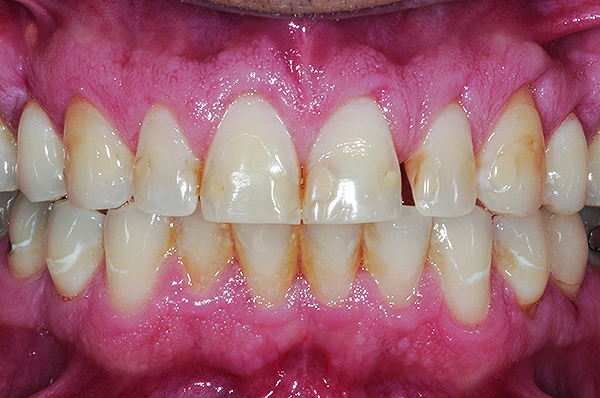

Fig 5. Preoperative view of patient requiring esthetic changes up to at least the bicuspids (Fig 5); postoperative view with CL-I feldspathic porcelain veneers up to the first bicuspid (Fig 6).

Figure 5

Fig 6. Preoperative view of patient requiring esthetic changes up to at least the bicuspids (Fig 5); postoperative view with CL-I feldspathic porcelain veneers up to the first bicuspid (Fig 6).

Figure 6